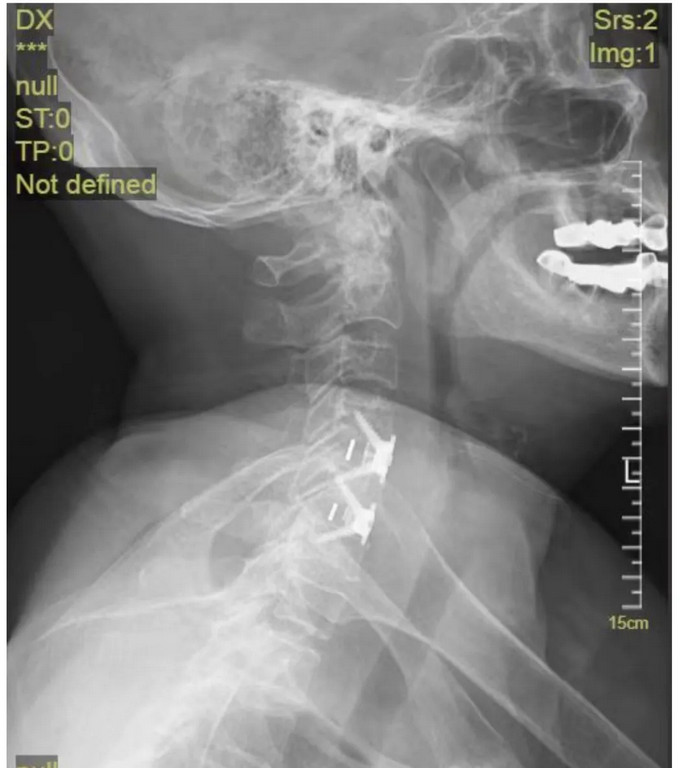

頸椎正位DR

頸椎側(cè)位DR